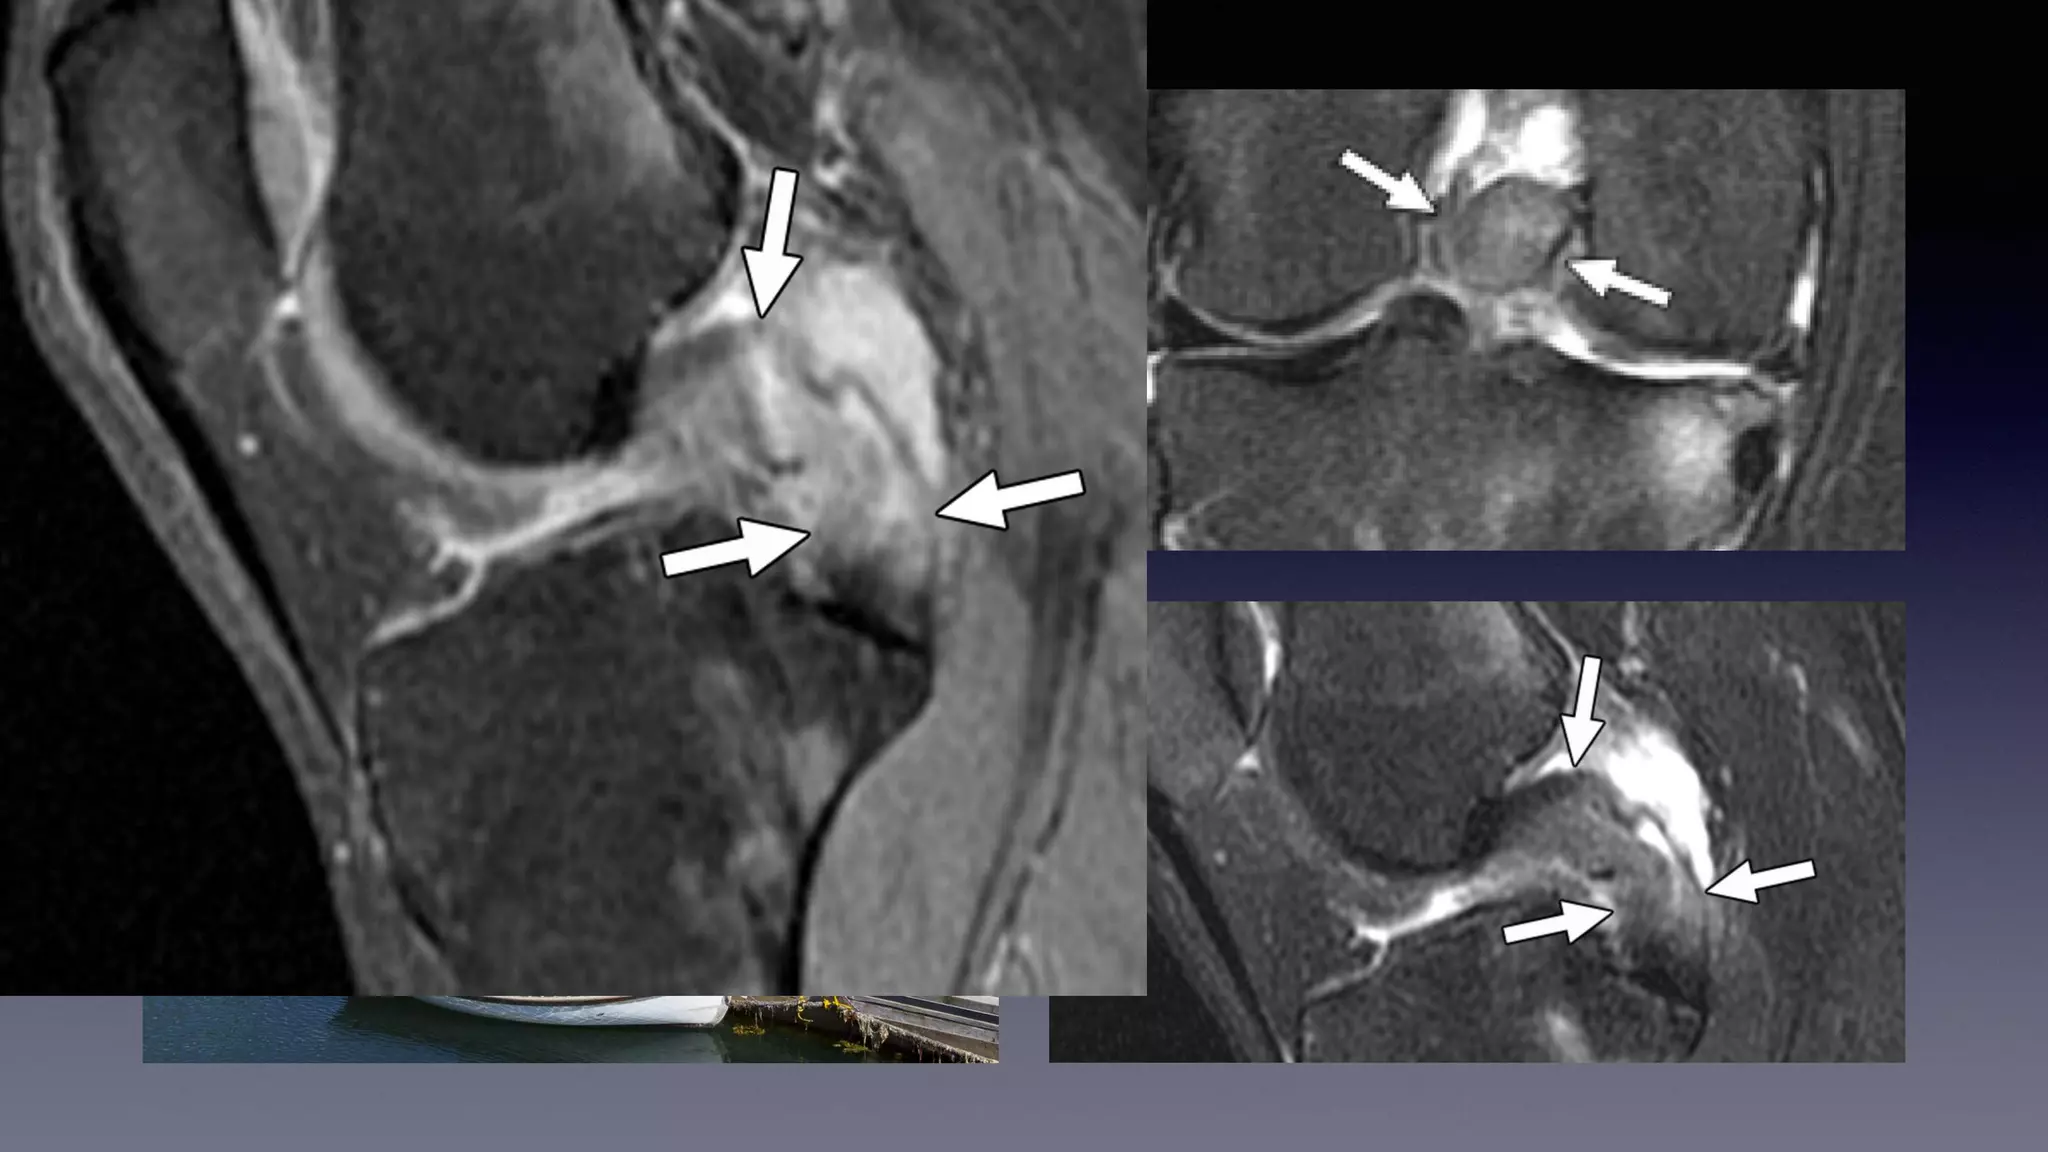

This document discusses using MRI to diagnose ligament injuries in the knee. It begins with an overview of MRI anatomy of the knee and expected pathology. It then discusses specific ligaments like the ACL, PCL, MCL and LCL. For the ACL, it shows images of acute tears, chronic tears and intrasubstance tears. It emphasizes knowing the knee anatomy well and correlating any abnormalities seen with clinical findings in order to apply the appropriate treatment.